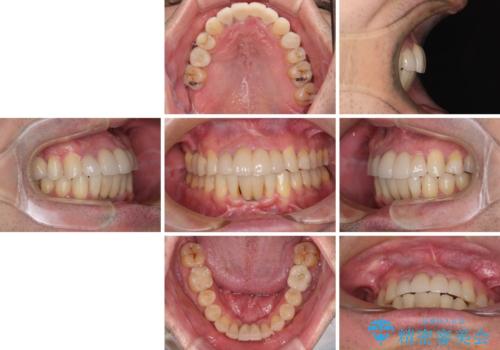

矯正治療を行いながら、欠損部はインプラントによる補綴治療を希望されたため、補助装置を用いたワイヤー矯正によりスペースを確保しながら歯列を整え、適宜インプラントを埋入していくこととしました。

上顎前歯もインプラントを希望していらっしゃいましたが、両隣の歯根が近接しており、インプラントは困難と判断したためオールセラミックブリッジによる補綴治療を前提として治療を開始することとしました。

下顎前歯にインプラントを2本埋入するのは非常に困難であり、どうしても歯肉位置に土台の金属色が見えてしまう仕上がりとなりました。無理をせずに1本のみの埋入とするか、ブリッジを提案しましたが、患者様の強い希望により、2本埋入することとなり、大変満足していただけました。